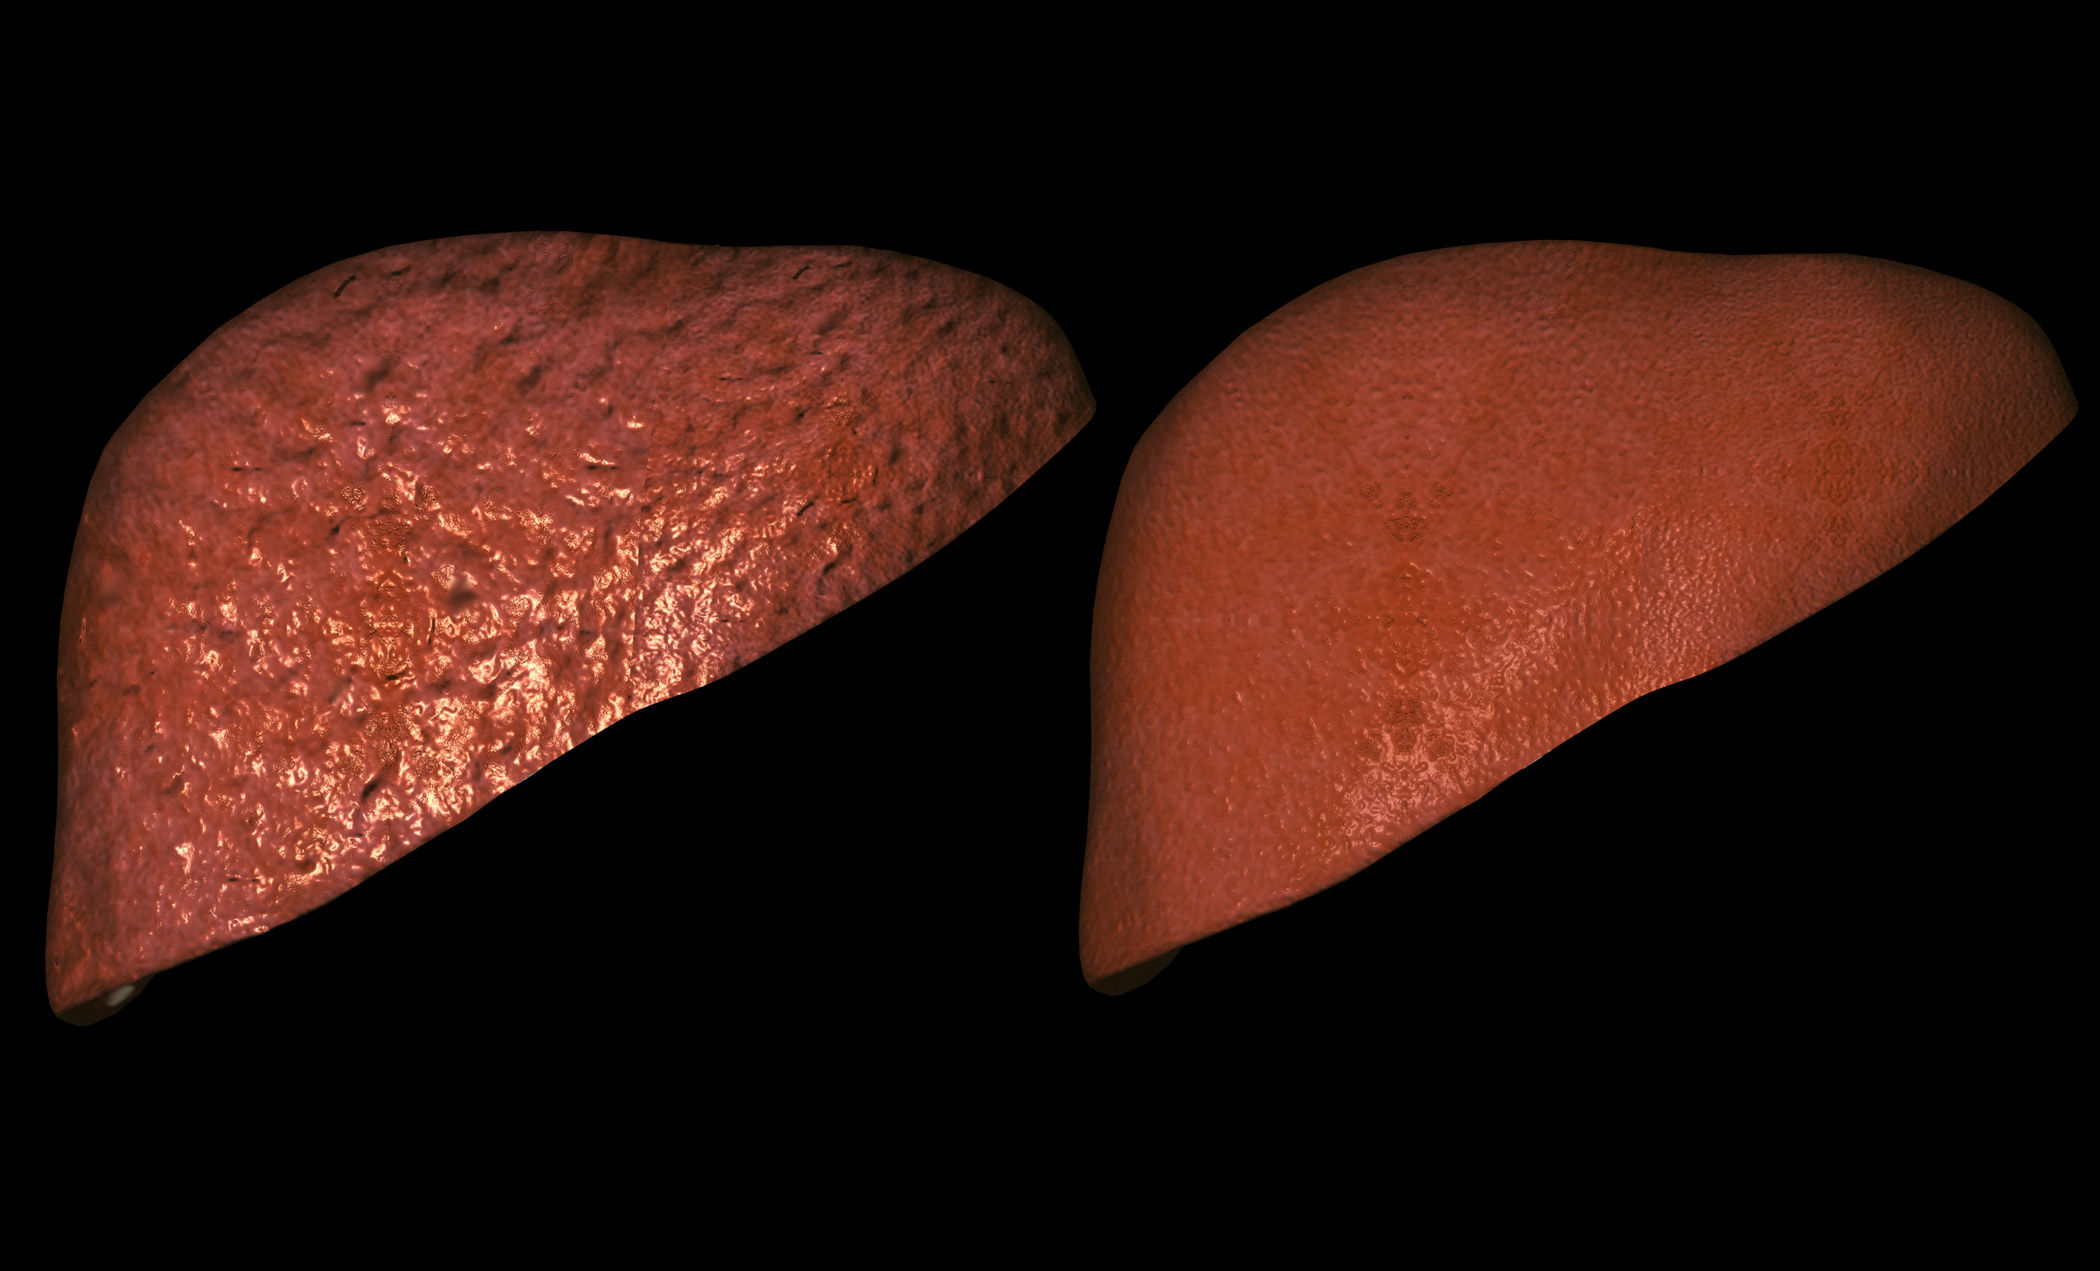

Изображения заболеваний печени: признаки и симптомы